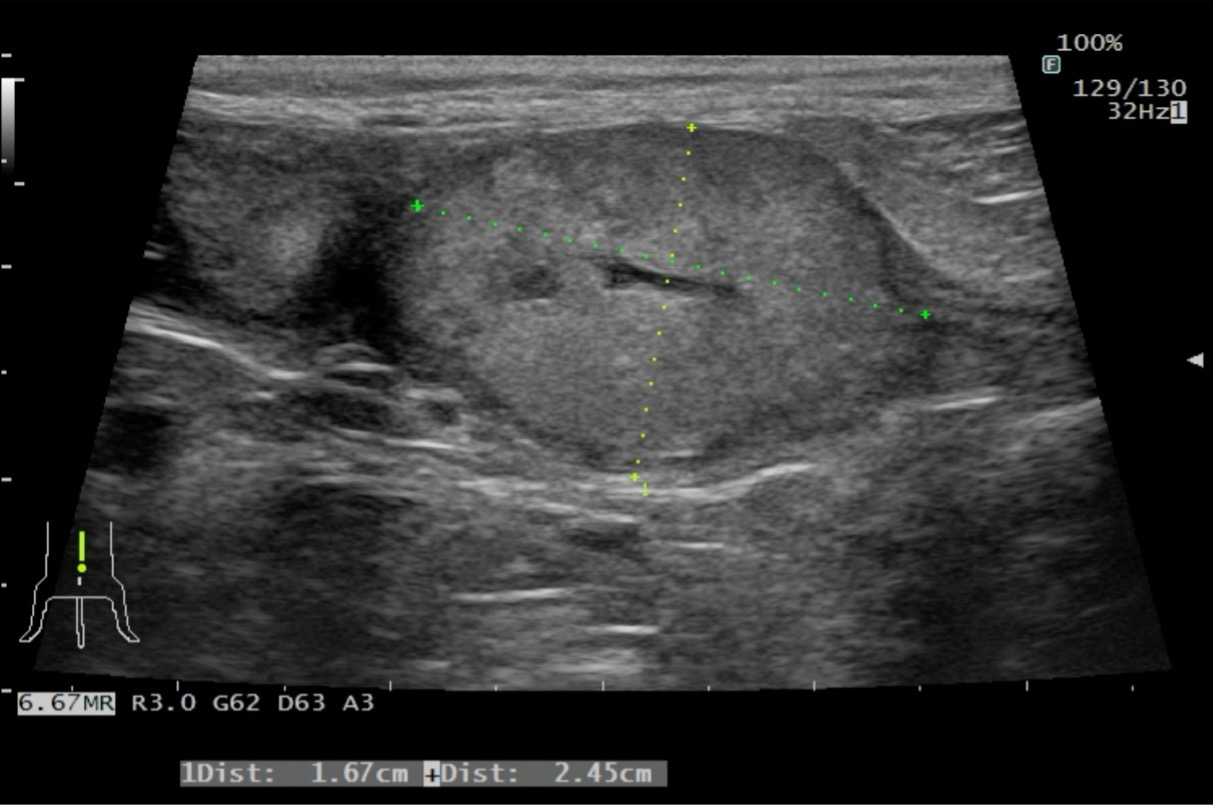

体重5.0kg(BCS3/5) 体温38.9℃ 心拍数114回/分 呼吸数30回/分 一般状態 :活動性100% 食欲100% 意識レベル 正常 一般身体検査 :特筆すべき異常所見なし 血液化学検査:異常所見なし 血液凝固系検査:TAT含め正常値 胸部X線検査:特記すべき異常所見なし 超音波検査:膀胱では膀胱頸部全周において腫瘤病変を認め、前立腺に連続する。この腫瘤は前立腺に主座し膀胱内へ伸展している形態である。(図1)前立腺の被膜構造は正常であり、腫瘤の膀胱外への浸潤は認められない。また周囲リンパ節は正常構造である。 尿道カテーテル採尿:尿沈渣では異型性を強く伴う大型の上皮系細胞が多数集塊を形成して認められる。